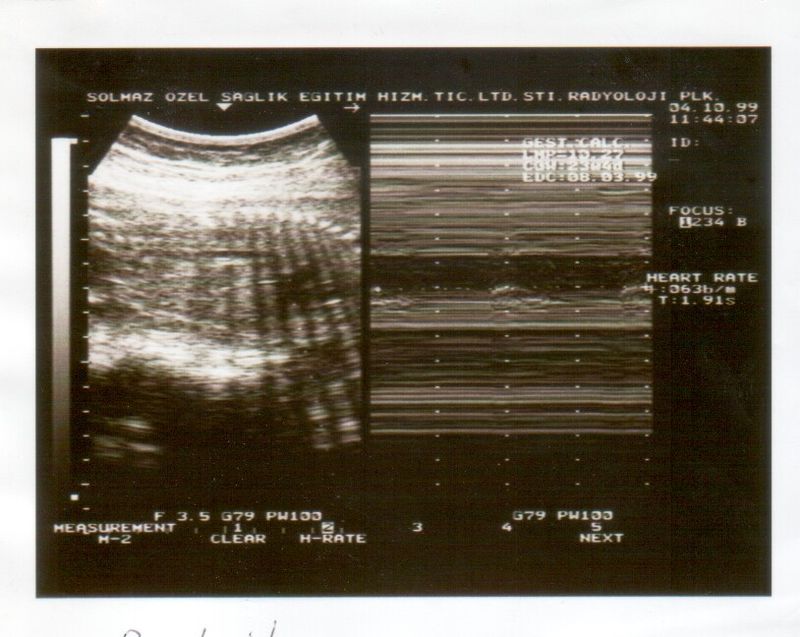

Enter biophysical profile scoring, a crucial tool that offers reassurance and clarity to mothers like Meera. This service is designed to assess the well-being of the fetus through a series of ultrasound and non-stress tests. It combines five critical measurements, providing a comprehensive overview of the baby's health and ensuring that expectant mothers can approach each step of their pregnancy with confidence.

Meera recounts her experience at the local clinic. “I remember the first time I heard about biophysical profile scoring. My doctor explained how it evaluates the baby's heart rate, muscle tone, movement, breathing, and the amount of amniotic fluid. It was a relief to know that there was a structured way to monitor my baby's health.”

At the clinic, the friendly staff guided her through the process. As she lay on the examination table, watching the ultrasound screen, she felt a wave of calm wash over her. The technician gently explained each part of the test, reassuring Meera that her baby’s development was right on track.